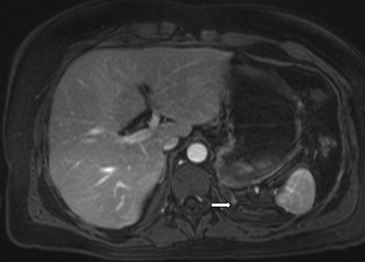

En la TC no contrastada las glándulas suprarrenales normales son homogéneas y simétricas, con una densidad muy similar a la del parénquima renal adyacente (Figura 1 a). Con un medio de contraste ev la glándula suprarrenal se opacifica en forma homogénea, similar al hígado o al bazo (Figura 1 b). Si la cantidad de tejido adiposo retroperitoneal es abundante las glándulas suprarrenales pueden aparecer enteramente rodeadas por grasa y su delimitación es más fácil (Figura 2 a); lo inverso ocurre en pacientes muy delgados con escasa grasa retroperitoneal (Figura 2 b). En RM, en secuencias ponderadas en T1 y T2 convencionales tienen una intensidad de señal homogénea, hipointensa respecto de la grasa adyacente e iso o hipointensa con respecto del parénquima hepático (Figura 3 a y b). En los cortes coronales se aprecia mejor la forma y la posición de las glándulas suprarrenales (Figura 3 c).

Figura 3. Glándula suprarrenal normal en resonancia magnética. (a) Cortes axial ponderado en T1 la señal de la glándula normal (flecha negra) es hipointensa respecto a la grasa retroperitoneal e isointensa respecto al parénquima hepático. (b) Cortes axial ponderado en T2 en que se muestra la glándula suprarrenal derecha (flecha blanca) y (c) corte coronal ponderado en T2 en que se muestra la glándula suprarrenal derecha (flecha blanca) y la glándula suprarrenal izquierda (flecha negra) con similares características de intendidad de señal. 3. Causas y prevalencia de las lesiones suprarrenales